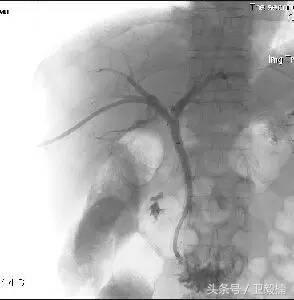

(1)经皮肝穿胆道引流(Percutaneous transhepatic choledochus drainage,PTCD或PTD)由于恶性(如胆管癌、胰头癌)或良性(如总胆管结石)病变,引起肝外胆道梗阻,临床出现黄疸。PTCD可行胆道内或胆道外胆汁引流,故而缓解梗阻,减轻黄疸,为根治手术提供有利条件。行PTCD前需先做经皮肝穿胆管造影(Percutaneous transhepatic),确定胆管梗阻的部位、程度、范围与性质。PTCD有内外引流之分,通过PTC的穿刺针引入引导钢丝,而后拔出穿刺外地,沿引导钢丝送进末段有多个侧孔的导管,导管在梗阻段上方的胆管内,其内口亦在该处,胆汁经导管外口连续引流,是为外引流;若导管通过梗阻区,留置于梗阻远端的胆管内或进入十二指肠,胆汁则沿导管侧孔流入梗阻下方的胆管或十二指肠,是为内引流。